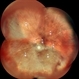

- Fundus image of 66-year-old WM with Hx of SBOD in 2009. presents with exposed SBOD and infection seen in accompanying images.